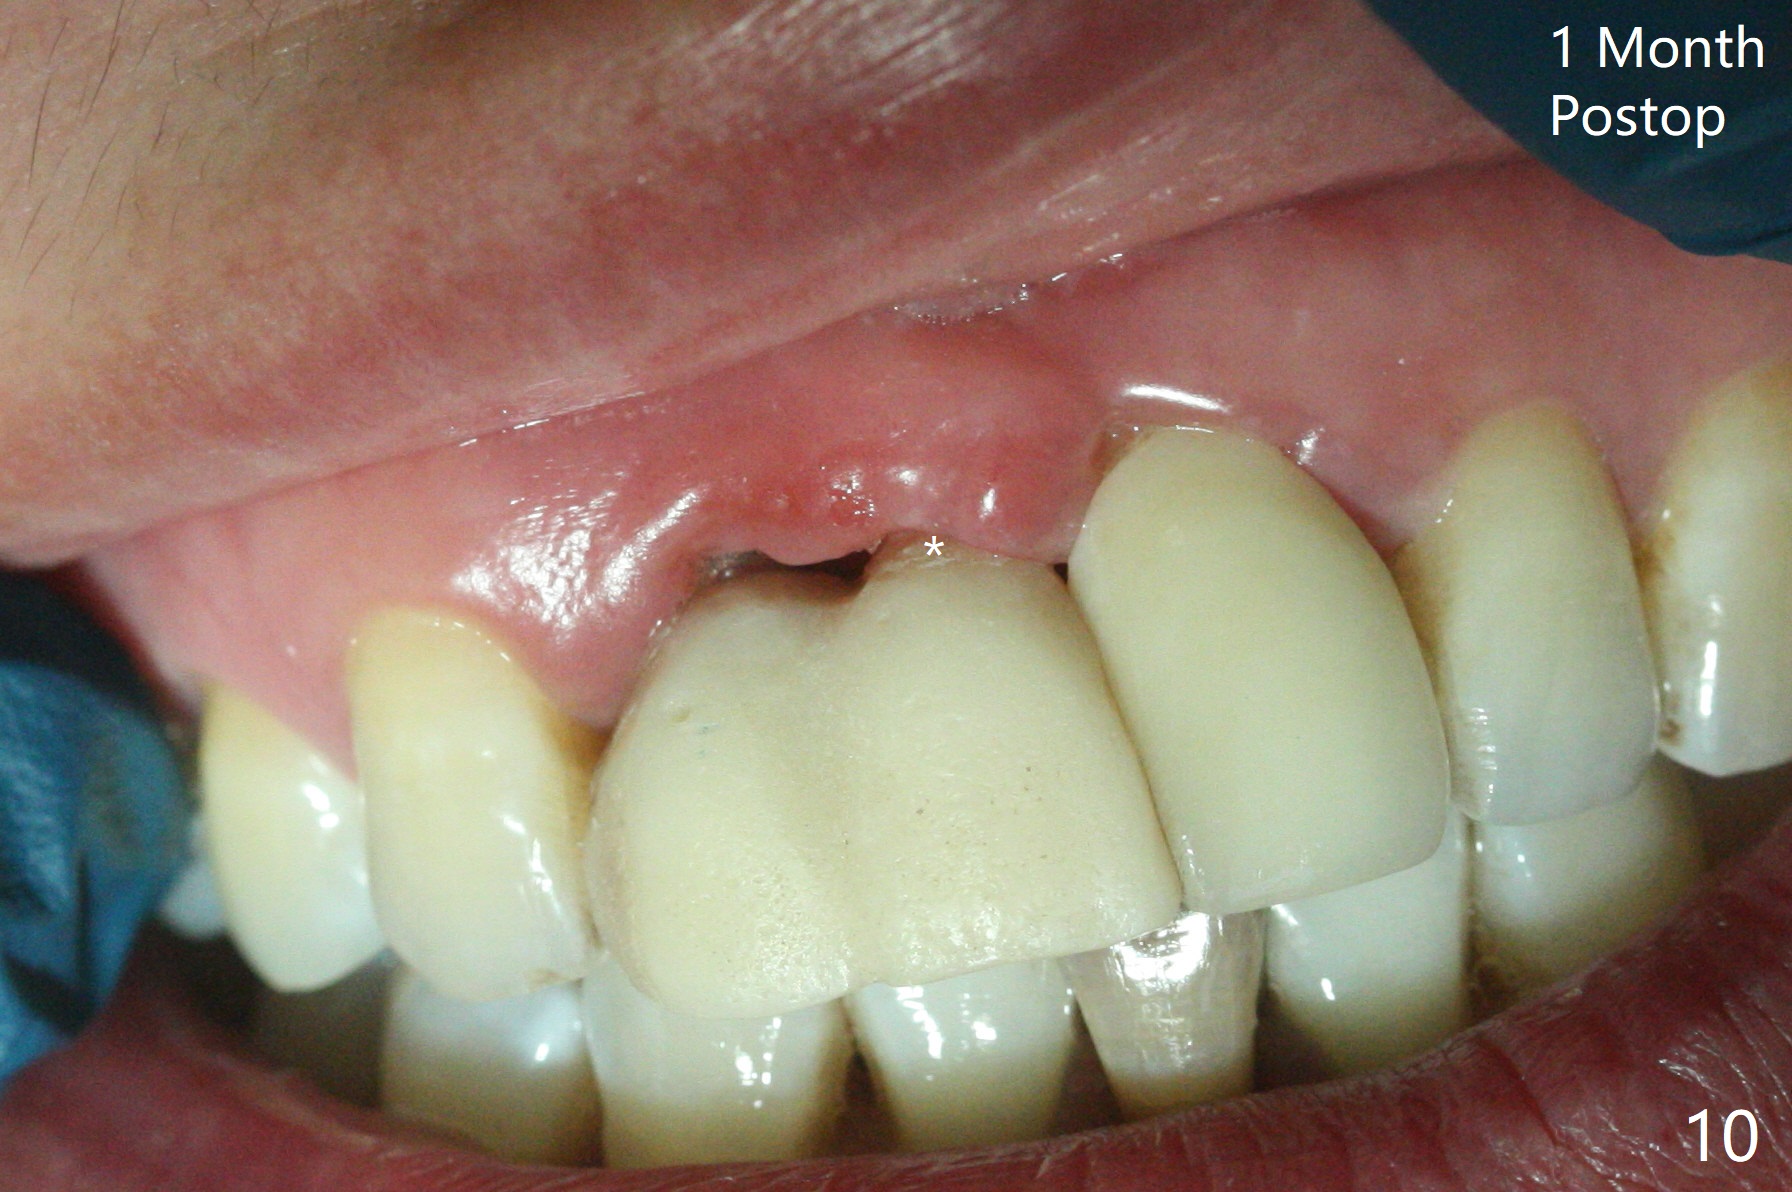

拆除部分桥发现:中,侧切牙牙龈红肿(图一),不利于切口和伤口愈合。不过还是在中切牙区切开,牙龈相当厚,有利于今后牙龈形成凹陷和乳头。坏消息是近远中距离太短,不利于植牙以及今后局部卫生维护,所以决定只在侧切牙种植(图二,三),完成钻洞后,颊侧根尖穿孔植骨,然后植入植体,即刻放置修复基台(图四 (*:牙龈乳头)),暴露基台牙龈缘,制作临时悬臂桥 (图五),两个中切牙牙冠长度差不多,插入临时桥时颊侧牙龈乳头基本形成(图六:*),缝合前颊侧,腭侧牙龈瓣下放置粘性骨块(图七,八:* )和PRF膜(图七:^)。最后使用牙周敷料。但愿术后牙龈炎症消失,形成良好牙龈乳头和pontic concavity。 其实由于口腔卫生习惯,术后十七天颊侧牙龈仍红肿(图九),而腭侧正常。如果口腔卫生改善而红肿依然存在,让实验室制作临时桥。术后一个月颊侧牙龈红肿好些(图十),好像骨粉丢失少许,可能与水枪使用有关。右上1牙冠显得太短(*)。也太肥大,因为右上1切缘太颊侧,与左上1对比(图十一:*)。由于颊侧牙龈(图十二:B)术中推向颊侧,与腭侧(P)牙龈之间放置大量粘性骨粉,术后一个月骨粉(<)形成牙龈,形成凹陷。颊侧萎缩不再明显了。右上1牙冠颈部多加些树脂,牙齿就显得长的多(图十三:箭头)。与侧切牙之间颈部故意留下间隙(*),让牙龈入位(空箭头),形成龈乳头。当右上1临时牙冠切缘(图十四:*)移到腭侧,外形改观不少。下次改善侧切牙唇侧。术后两个月三个星期牙龈红肿好像减轻,牙龈没有进入切牙间隙,干脆用树脂关闭(图十五:> <)。下次减少侧切牙切缘(^),适当增加中切牙长度(上提牙龈)。术后3.5个月植体好像整合,基台完全就位(图十六)。术后3.5个月Pontic凹陷形成,但是1,2之间龈乳头始终无法形成(图十七)。以后类似病例应该多种植一个。此例草率取模,可能需要临时粘固,观察植体近中颊侧所谓瘘道,必要刮治。由于比色不佳,需要实验室颜色更改,病人强化卫生,术后七个月,永久性牙冠粘固前,局部牙龈健康(图十八)。